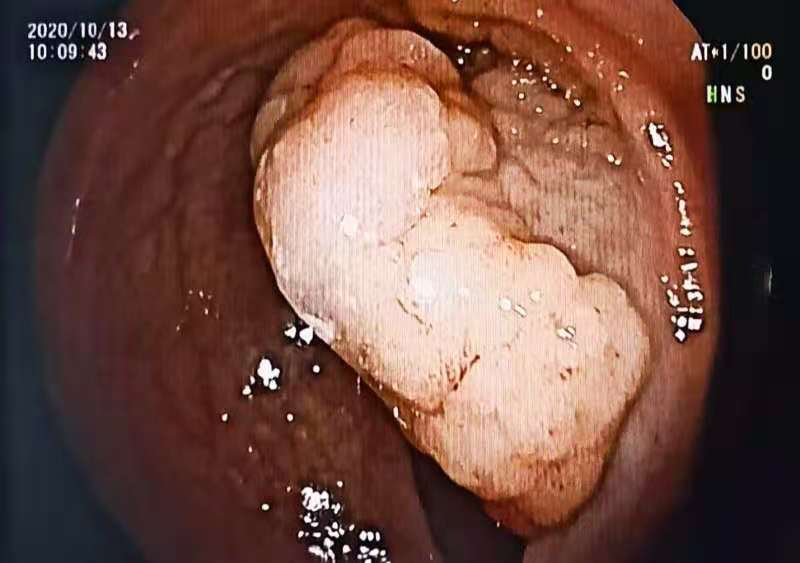

患者刁某某,女,71岁。主因:“排便不畅,大便习性改变3月余”,就诊于大同守佳消化病医院。行结肠镜检查示:直肠距离肛门15cm处,可见一菜花样肿物,大小约4.0*4.0*2.0cm。病理回报:高级别内瘤变。行超声内镜示:肿瘤限于黏膜层。

结肠镜检查

术前结肠镜显示